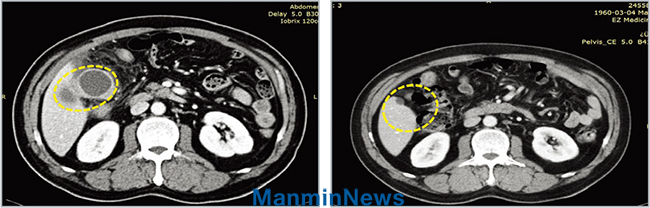

±è¹®»ý Áý»ç(59¼¼, Çѱ¹)´Â 2017³â 6¿ù, °©Àڱ⠽ÉÇÑ º¹ÅëÀÌ ÀϾ °Ë»ç¸¦ ÇØ º¸´Ï ±«Àú¼º ´ã³¶¿°À̾ú´Ù. CT ÃÔ¿µ °á°ú, ´ã³¶¿¡ ¿°ÁõÀÌ ½ÉÇϰí ÀϺκÐÀº ³ì¾Æ¼ °í¸§ÀÌ ÁÖº¯À¸·Î ÆÛÁ® ÀÖ¾ú´Ù. ÆÐÇ÷Áõ±îÁö ÁøÇàµÉ ¼ö ÀÖ´Â »óȲÀ̾ú´Ù. ±×·¯³ª ¹ÏÀ½À» ³»º¸¿© ÀÌÀç·Ï ¸ñ»ç¿¡°Ô ±âµµ¸¦ ¹ÞÀº µÚ¿¡´Â ÀÌ¹Ì ³ì¾Æ ÅÍÁ®¹ö·È´ø ´ã³¶ÀÌ Á¤»óÀ¸·Î ȸº¹µÇ¾ú´Ù. ¹°·Ð Ç×»ýÁ¦³ª ÁøÅëÁ¦ °°Àº °ÍÀº ÀüÇô »ç¿ëÇÏÁö ¾Ê¾Ò´Ù.

CT ÃÔ¿µ

±âµµ¹Þ±â Àü: ´ã³¶ÀÌ ±«»çµÇ¾î õ°øµÇ¾úÀ¸¸ç ÁÖº¯ ¿°Áõ ¹ÝÀÀÀÌ ½ÉÇÔ. ±âµµ¹ÞÀº ÈÄ: ±«»çµÈ ´ã³¶ÀÌ ±âµµ¸¦ ¹Þ°í Á¤»óÀ¸·Î ȸº¹µÊ.